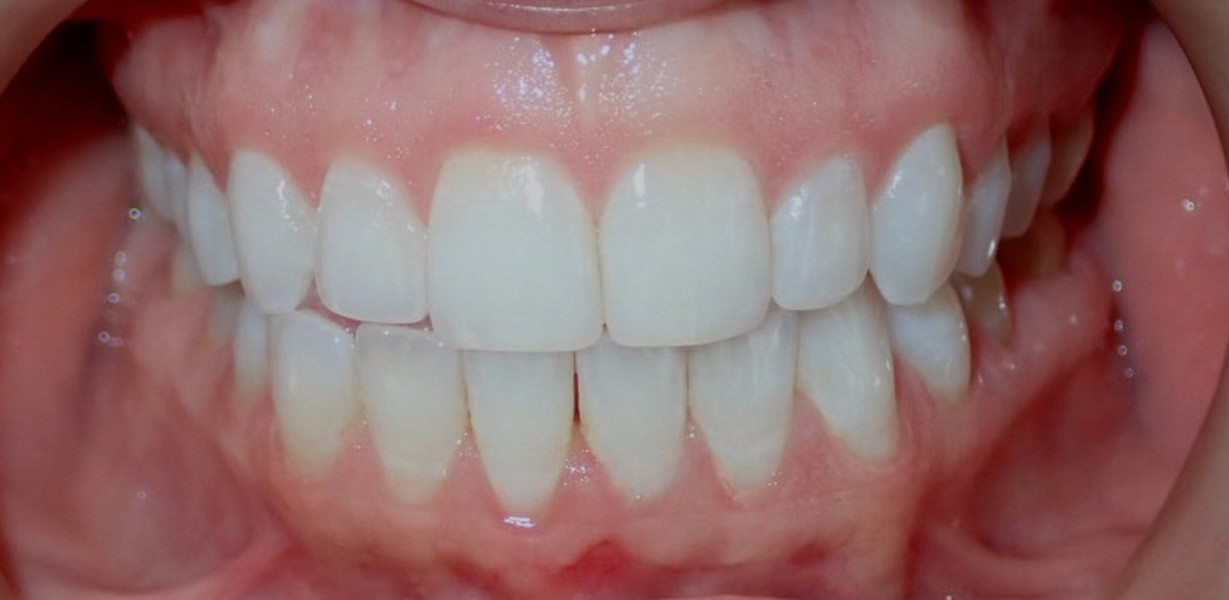

Final results

INTRAORAL